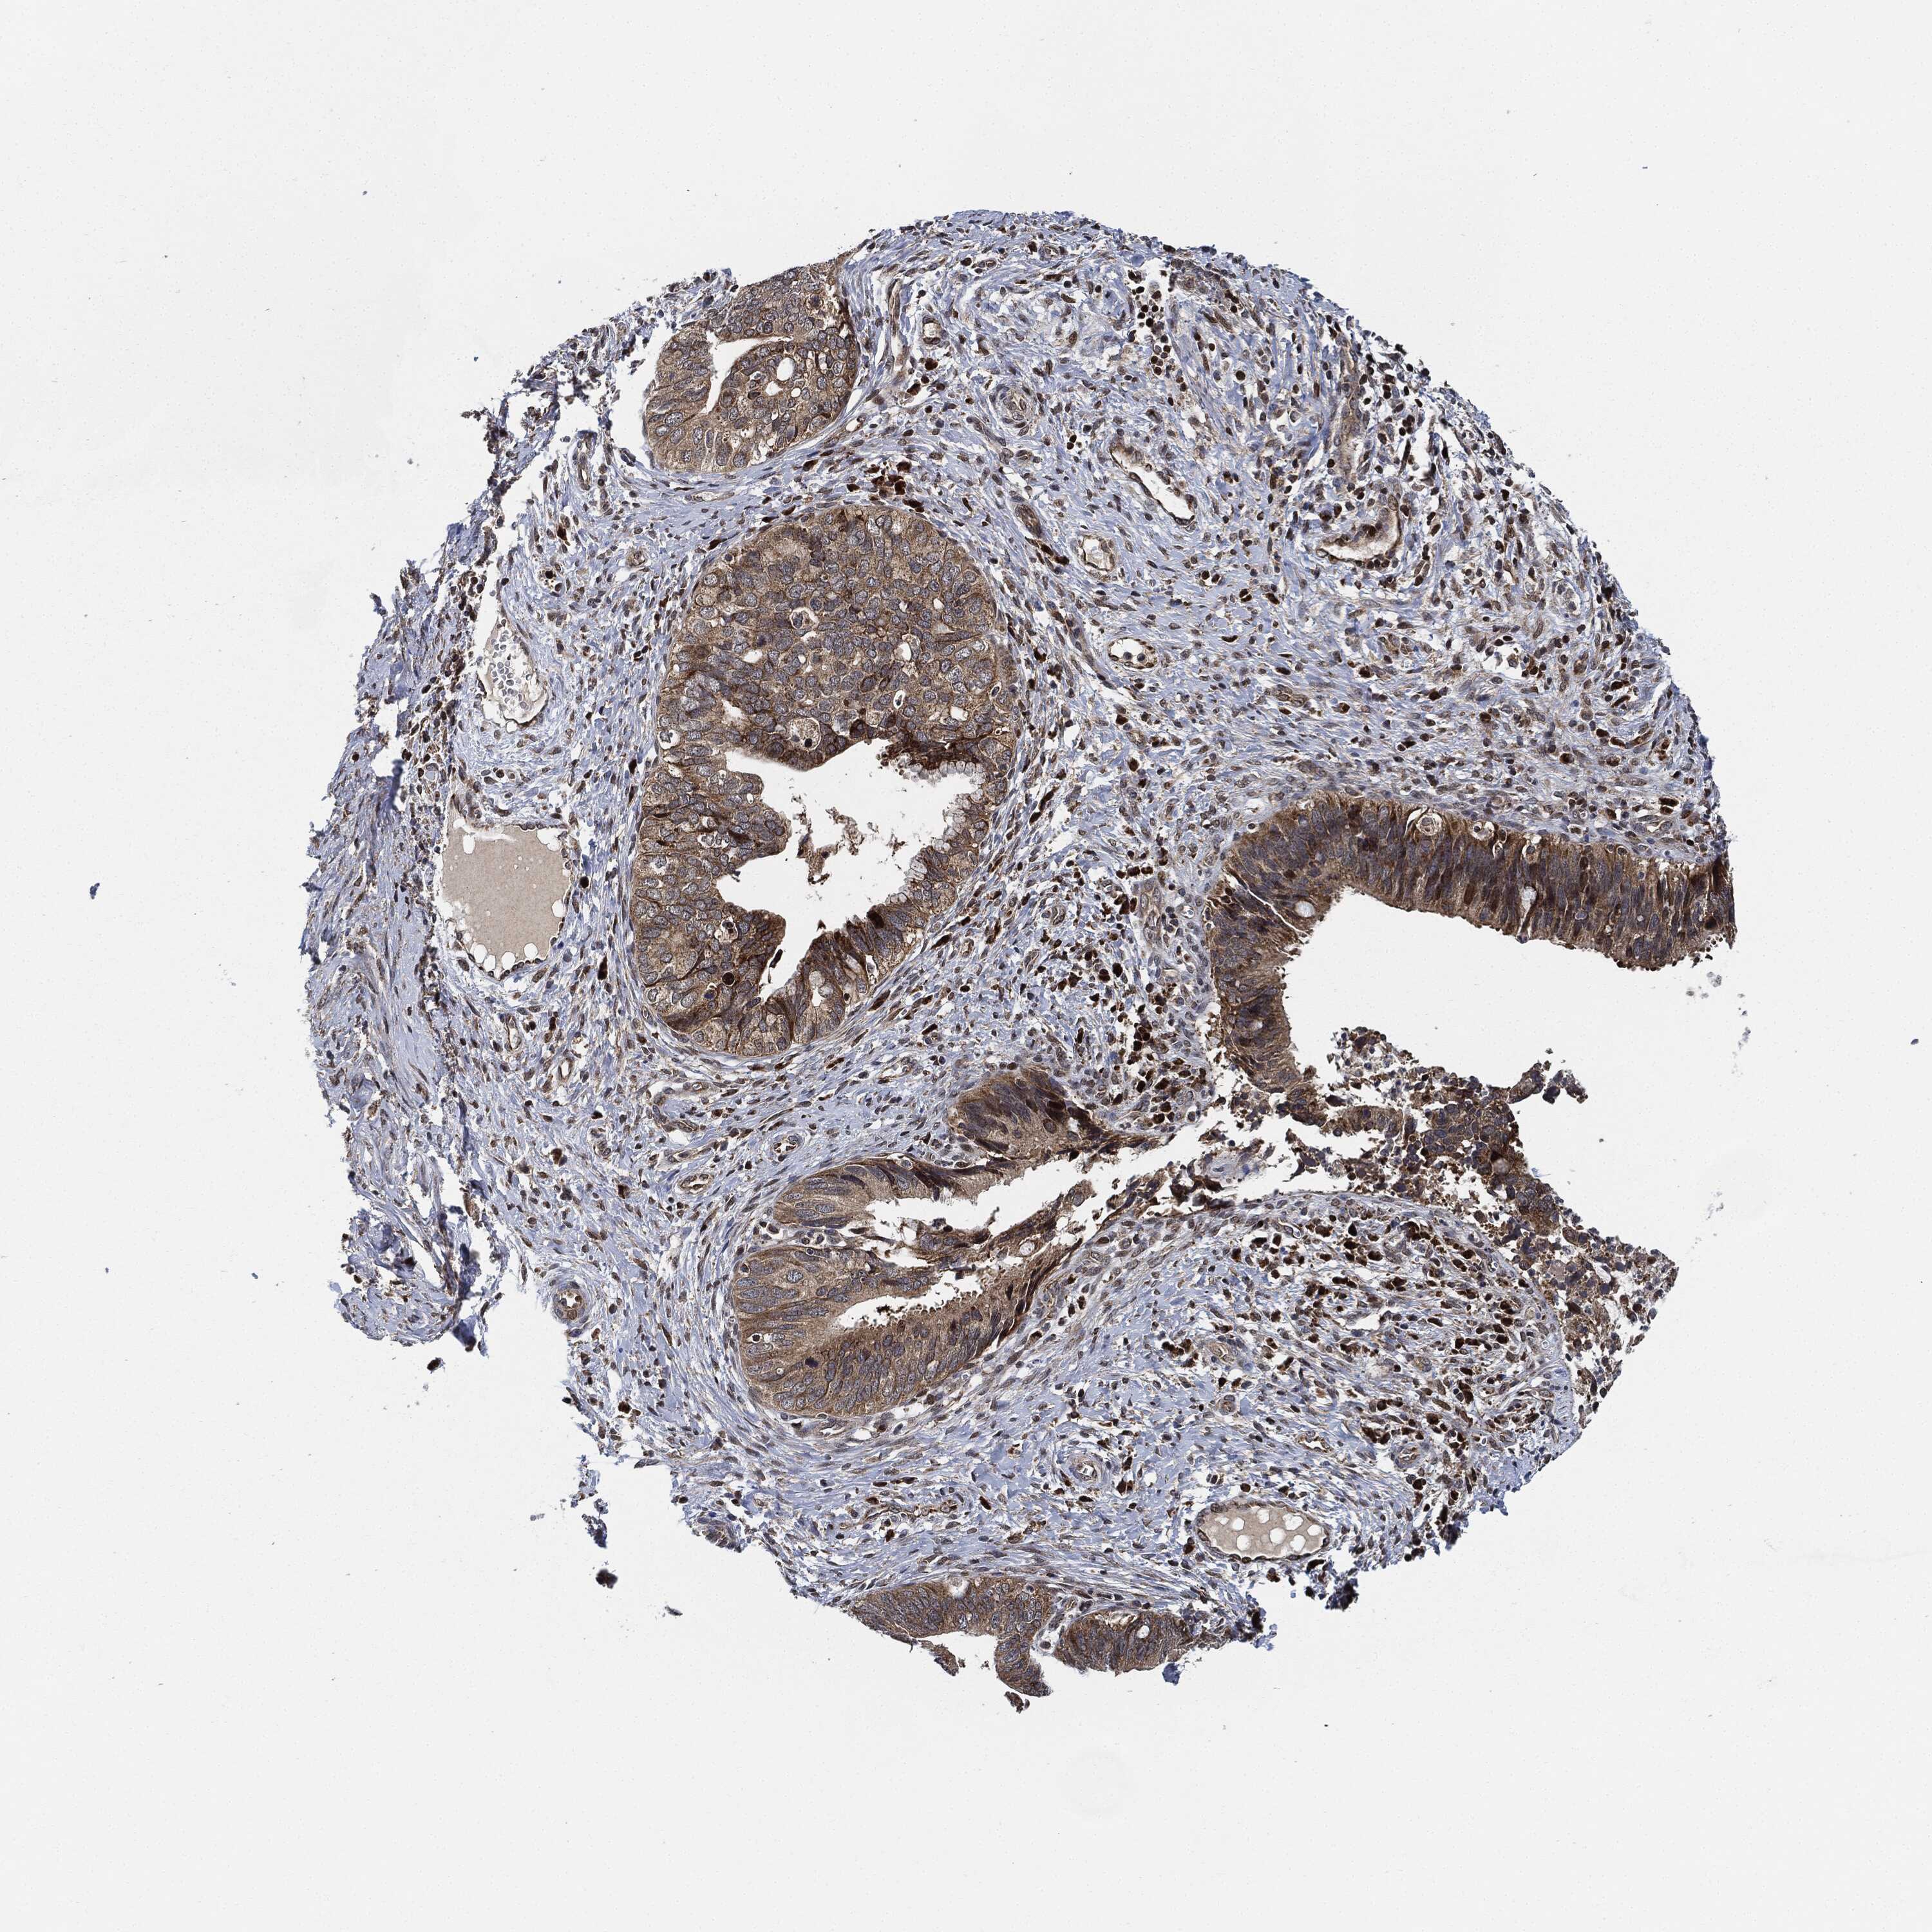

CERVICAL CANCER - Protein expressioni

A mouse-over function shows sample information and annotation data. Click on an image to view it in a full screen mode. Samples can be filtered based on level of antibody staining by selecting one or several of the following categories: high, medium, low and not detected. The assay and annotation is described here.

Note that samples used for immunohistochemistry by the Human Protein Atlas do not correspond to samples in the TCGA dataset.

Antibody stainingi

Antibody staining in the annotated cell types in the current human tissue is reported as not detected, low, medium, or high, based on conventional immunohistochemistry profiling in selected tissues. This score is based on the combination of the staining intensity and fraction of stained cells.

Each image is clickable and will lead to virtual microscopy that enables deeper exploration of all samples and also displays staining intensity scores, fraction scores and subcellular localization as well as patient and tissue information for each sample.

Antibody HPA002633

Adenocarcinoma, NOS

Squamous cell carcinoma, NOS